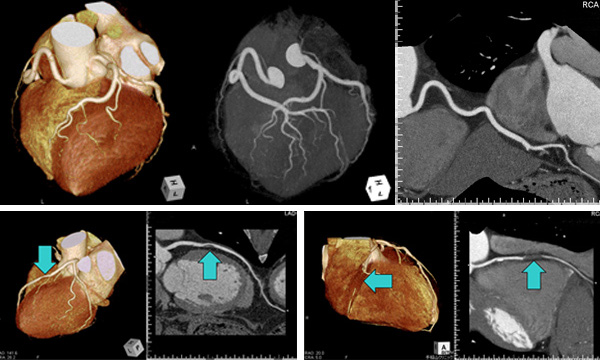

64列マルチスライスCT装置

当院では、世界最高水準の放射線画像診断装置である「64列マルチスライスCT」を導入いたしました。この装置は瞬時に64断面(スライス)が同時撮影できるマルチスライス技術を搭載し、頭部、胸部、腹部、心臓等の断層像(輪切り)や立体像(3D)の鮮明な画像が得られ、従来のCTでは診断できなかった冠動脈の病変(心筋梗塞や狭心症の原因)も確認でき、質の高い検査が行えます。 その他、脳動脈瘤や全身の動脈硬化の重症度判定、肺・肝・膵・腎などの早期癌の有無にも威力を発揮します。また、撮影時間の大幅な短縮により患者様のご負担も大幅に軽減されます。 心臓病の早期発見などに非常に有用です。

当クリニックで撮影した心臓のCT画像